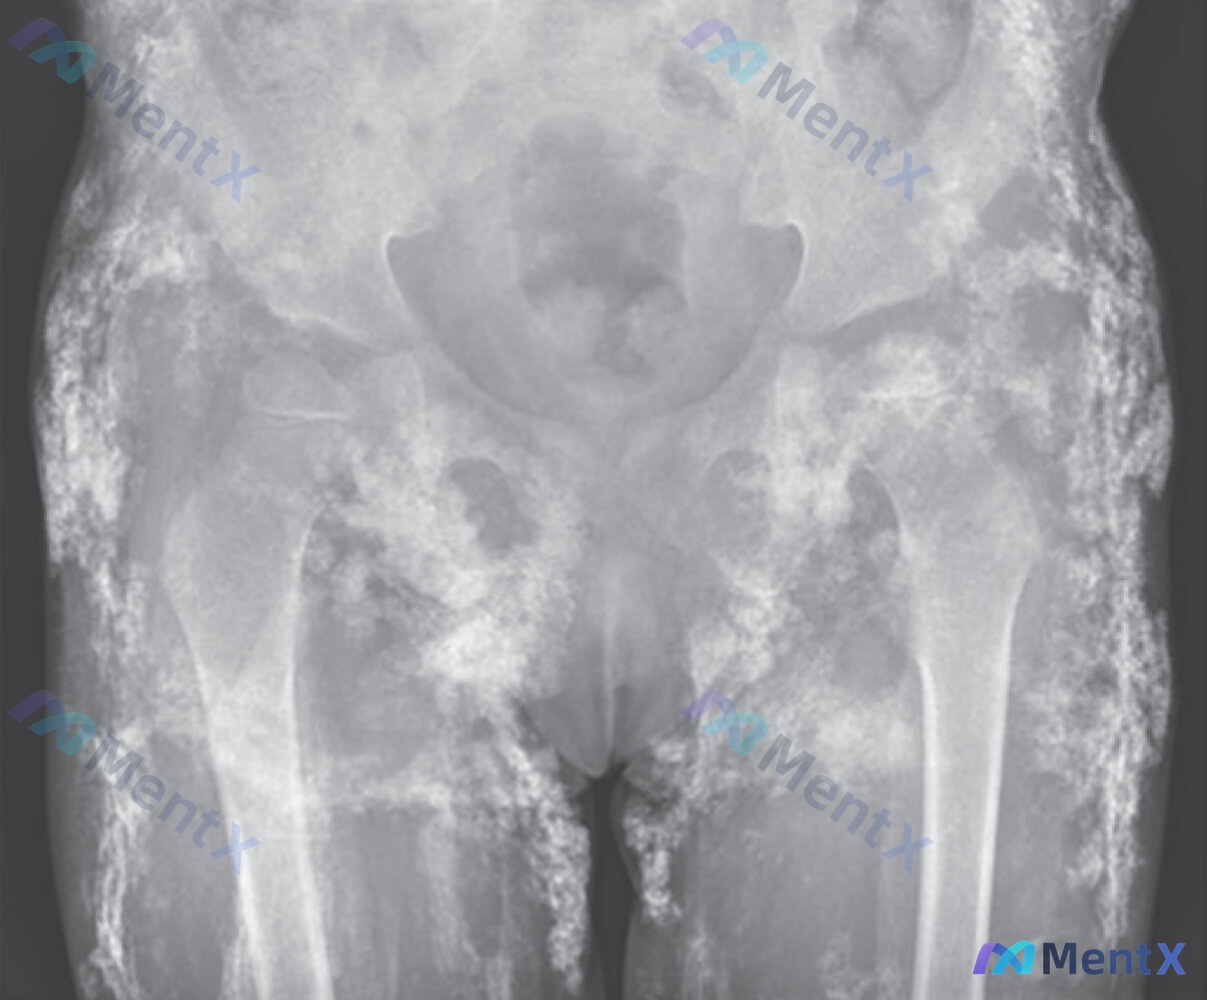

最近在整理资料时看到这个病例,觉得几个点结合得非常典型,尤其是影像学和抗体的对应关系,分享一下我的思路。 病例核心信息 - 患儿:4岁女童 - 病程:1年,慢性进展 - 主诉/现病史:最初双侧腿痛、右侧跛行,布洛芬暂时缓解;数月后加重,虚弱、上楼困难、需人抱 - 关键体征: ✅ 高尔征(Gower征...